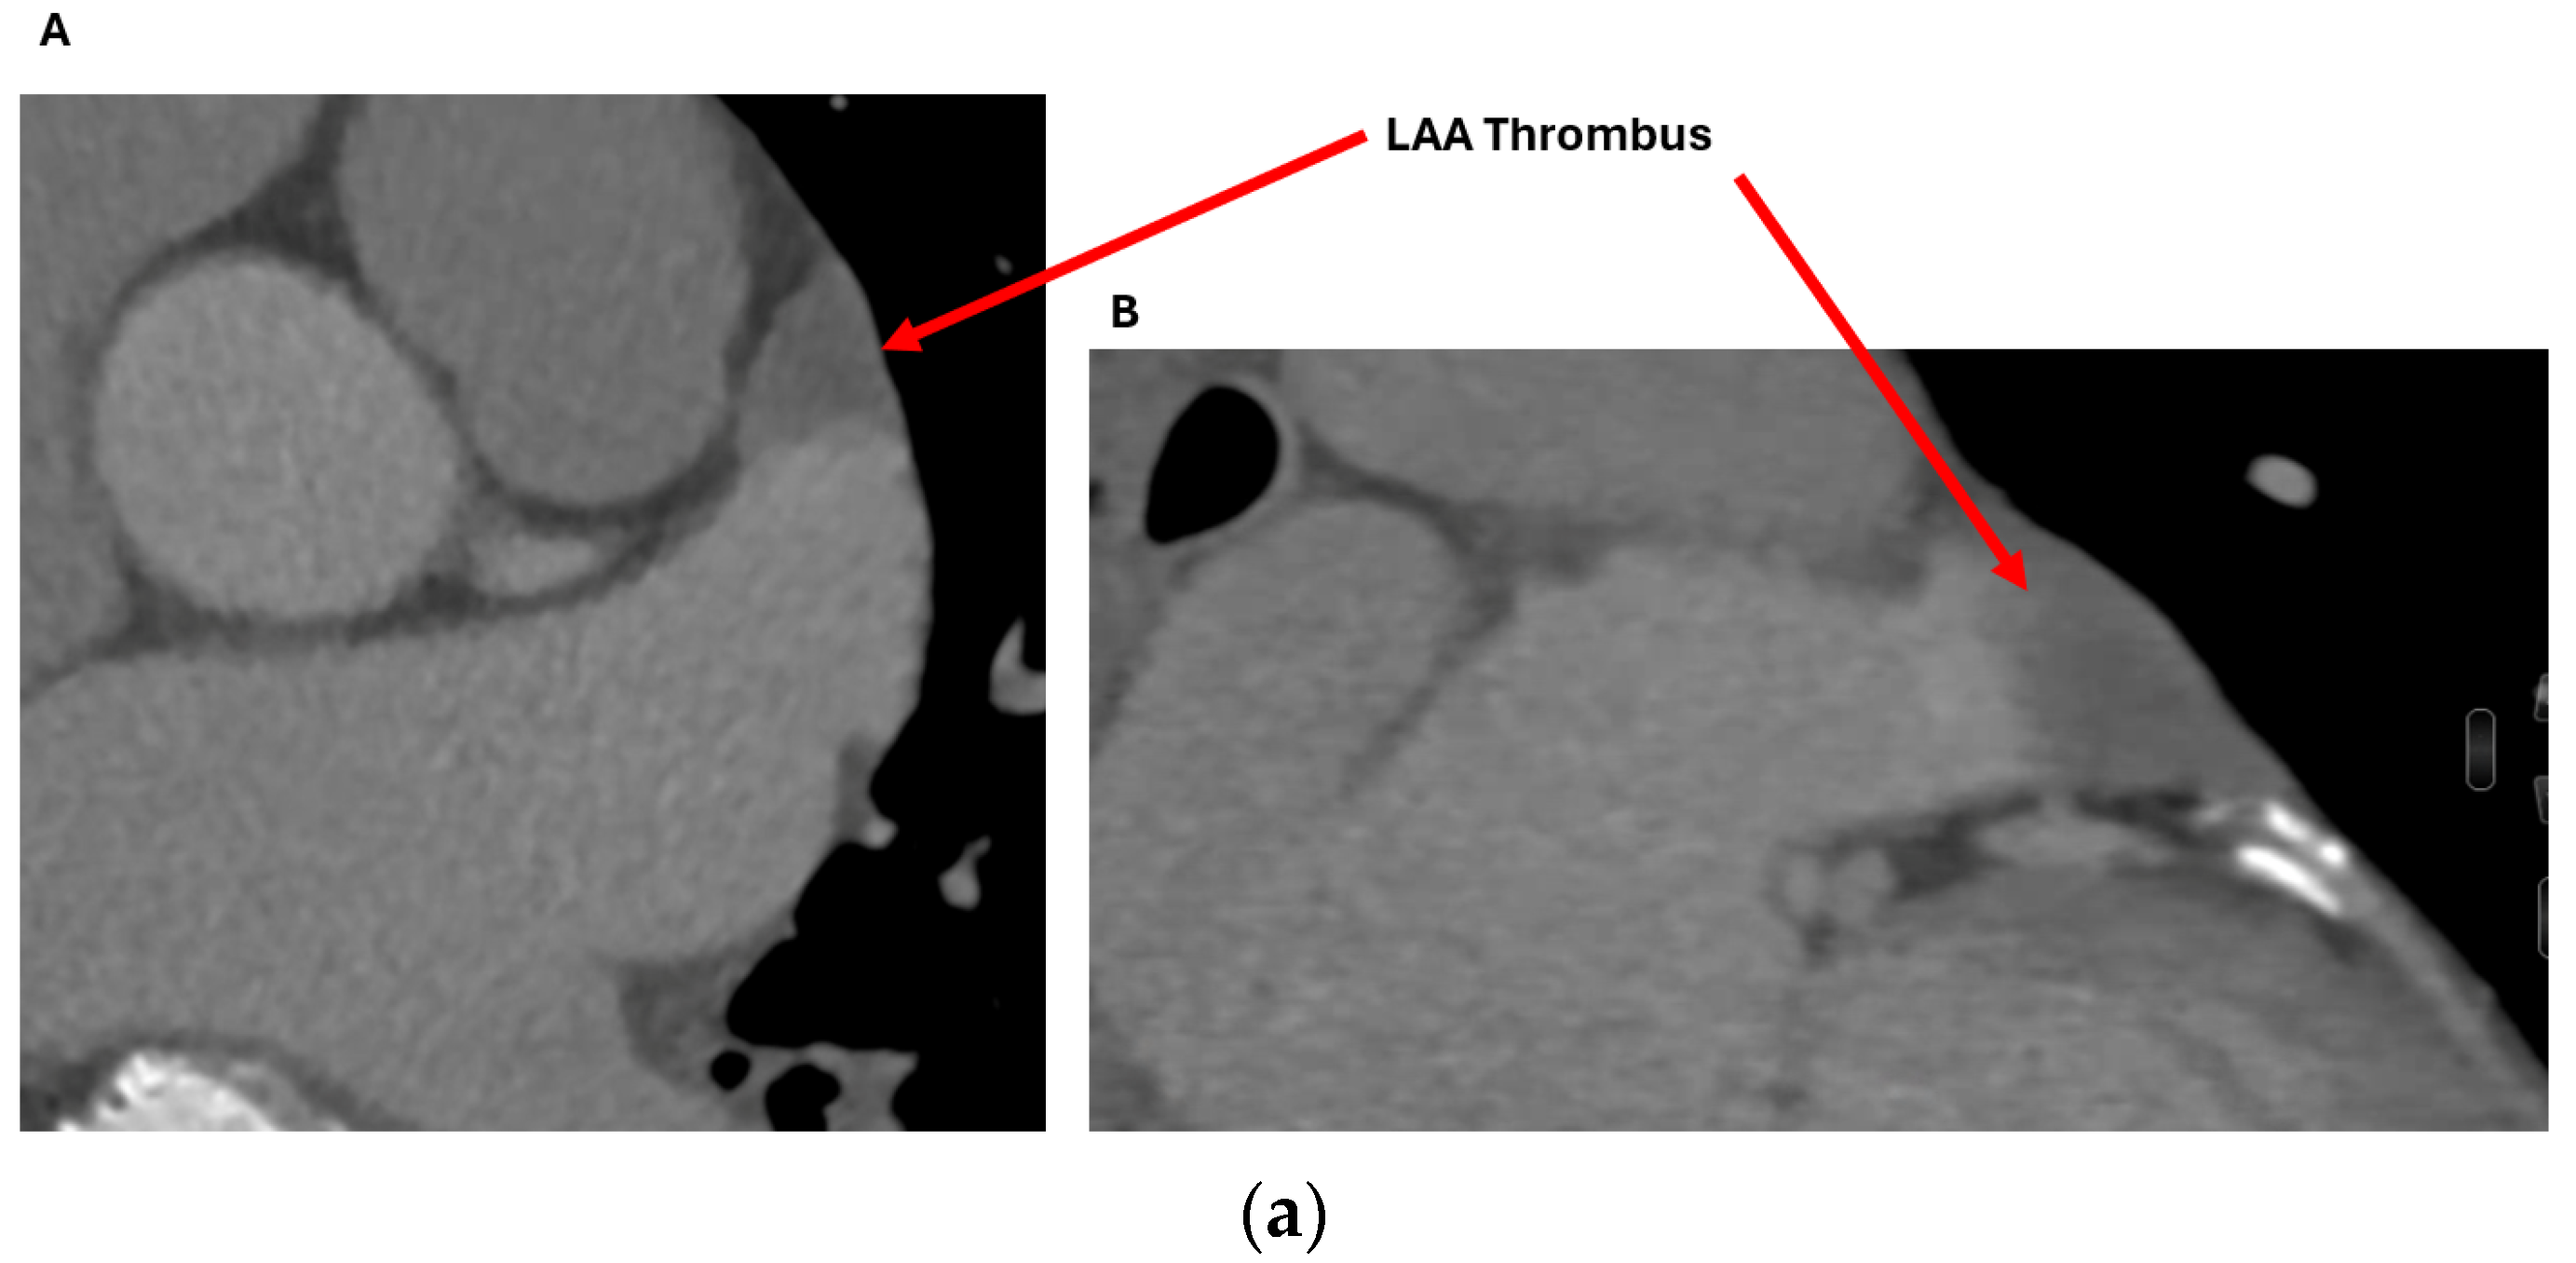

2.1.1. Anatomical Contraindications

2.2.1. LAA Thrombus Assessment